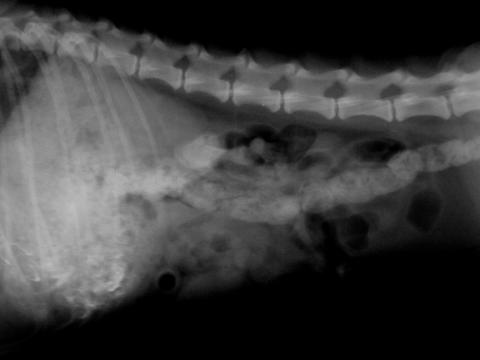

こっからが、私にとっては本題になるのですが、私は動物病院を営んでおりまして、一応獣医師の資格を持っています。

現在、私の病院では未だにアナログのレントゲンを使用していて、簡易な画像処理をかけるのもいちいちPCに写真を取り込んで、処理ソフトにかけて見るという、とてもめんどくさいことをしていました。

試しに、KALOSの内蔵カメラで撮影したところ、読映に支障の出るほどの画像の劣化が起こらなかったのでレビューしてみます。

同程度の拡大率で表示しているのですが、この時点だと、生のレントゲン写真のほうが広範囲が見られるので、いいように思えます。しかし、

見ればわかると思いますが、画像を拡大できるので背骨を重点的に拡大してみました。

かなり細かく、肉眼では見落としそうな部分まではっきり認識できます。

この機能を使えば、生のレントゲン写真でおかしなところに当たりをつけて、KALOSをつかって細かなところを見るということもできると思います。